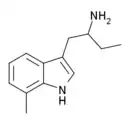

α-Alkyltryptamines are a group of substituted tryptamines which possess an alkyl group, such as a methyl or ethyl group, attached at the alpha carbon, and in most cases no substitution on the amine nitrogen.[17][18][19] α-Alkylation of tryptamine makes it much more metabolically stable and resistant to degradation by monoamine oxidase, resulting in increased potency and greatly lengthened half-life.[19] This is analogous to α-methylation of phenethylamine into amphetamine.[19]

αMT | 1-(1H-Indol-3-yl)propan-2-amine | 299-26-3 |